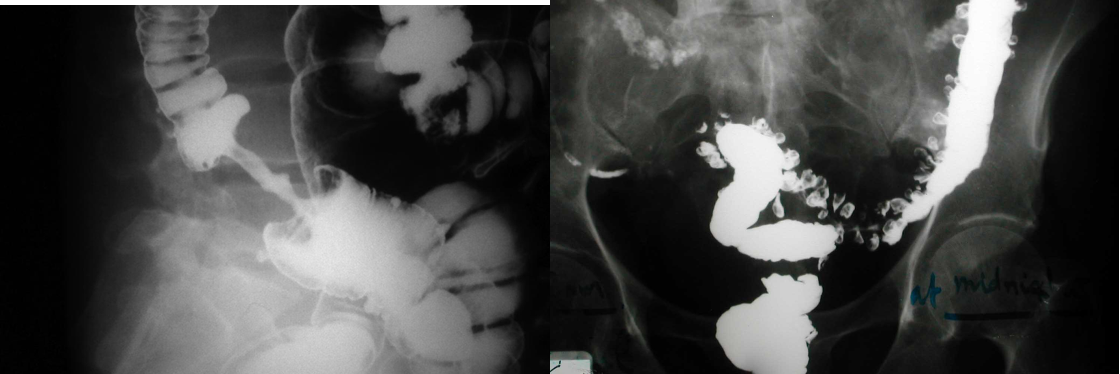

Contrast Imaging

Gastrograffin swallow, Barium meal / enema

- Visualize GI tract

- Single/ double contrast

- Inferior to endoscopy

Modality: Gastrography swallow / Barium Enema Findings: apple core / out pouching lesions Differentials: colon cancer / diverticulum

- barium swallow - zenkers diverticulum

- b swallow - diltation upper, stricture (diff cancer)

- normal (mucosal fold roge)

- dilated esophagus, stricture, bear beak/rat tail sign = aclasia

- follow through normal

- follow through (diff celiac; villus atrophy)

- barium enema from below

- apple core - neck and shoulder - stricture (cancer)

- Ulcerative collitis loss of haustration

- double enema - polyps